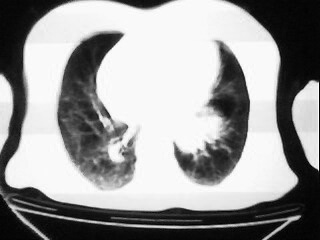

女,79,咳 嗽月余,无其它不适

1)两肺炎症。2)食管裂孔疝可能;建议行上消化道钡餐检查。

后纵隔内左心房至肝左叶后方椎体中线偏左巨大软组织包块,其壁均匀比较薄,其内可见宽气液平。

考虑食管裂孔疝。建议钡餐检查